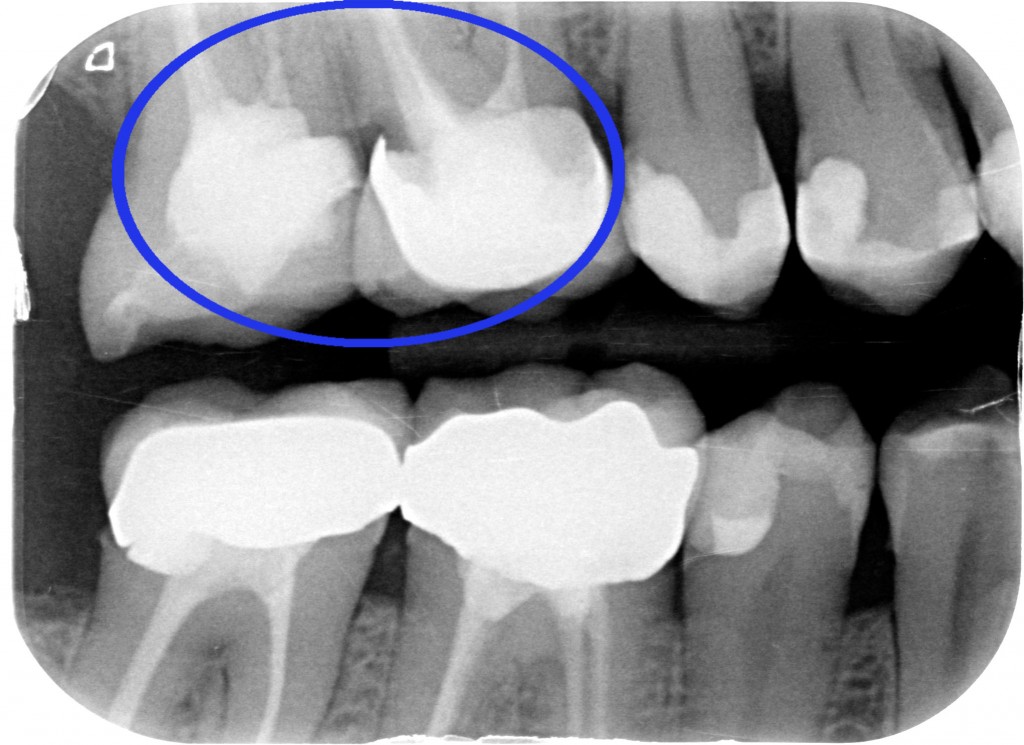

Accademicamente potremmo dire: CARIE SECONDARIA A CARICO DI 1.6 PRECEDENTEMENTE RESTAURATO MEDIANTE CORONA IN METALLO CERAMICA.

Ma io nella mia testa dico “chi ha fatto quella corona avrebbe dovuto fare un allungamento di corona clinica, ma non lo sapeva o non lo voleva fare. Quindi non ha potuto gestire correttamente il margine di chiusura distale. Quindi è rimasto del tessuto cariato o non è stato effettuato un corretto sigillo marginale per cui… E’ SUCCESSO IL FATTACCIO!”

Anche se il paziente non avvertiva nessun fastidio abbiamo fatto una visita completa, che comprende le due bite-wings posteriori e ci siamo accorti del problema. Ora però lo dobbiamo risolvere. Abbiamo tre strade: